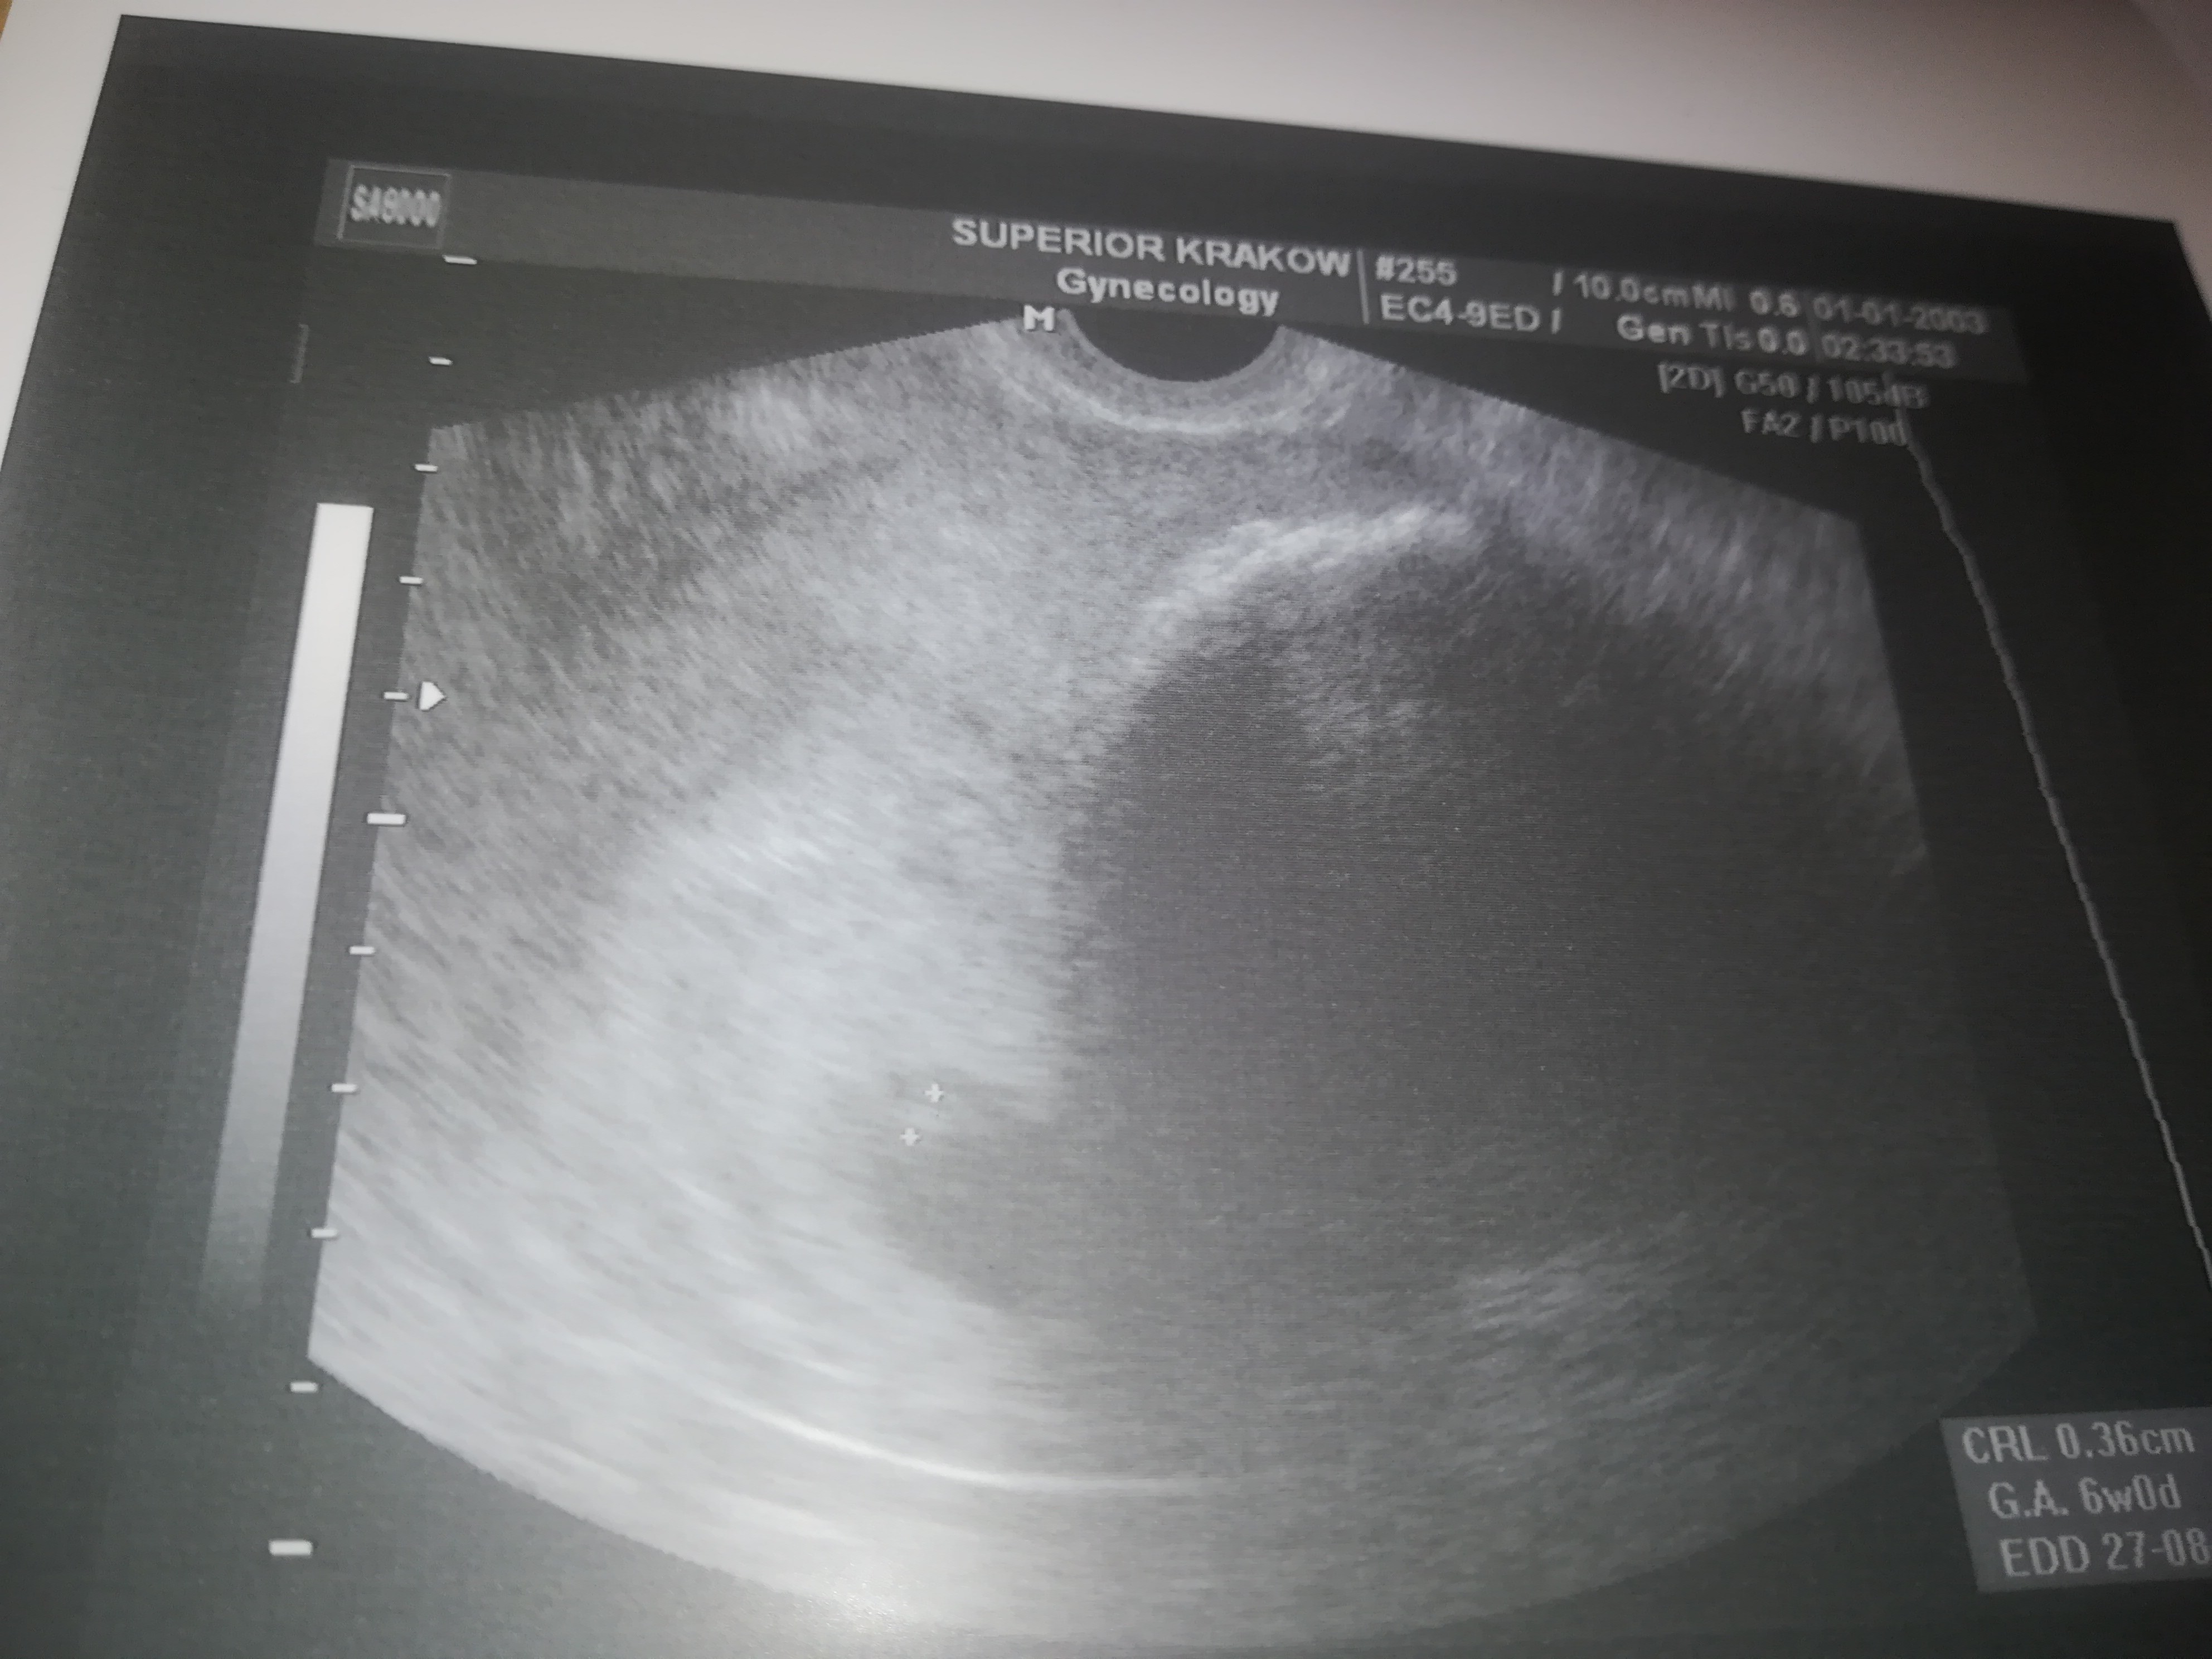

Na zdjęciu to wielkie po prawej stronie to miesniak a zarodek maleńki między plusikami.

Załączniki

• IMG_20191002_105203_1.jpg

IMG_20191002_105203_1.jpg

1,2 MB · Wyświetleń: 122